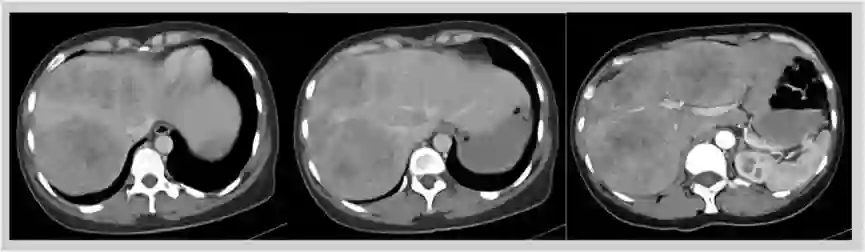

2017-11-03 腹部CT增强:肝内见多发团块高低密度混杂影,增强后动脉期可见边缘强化伴内部网格状强化。乙状结肠近直肠肠腔狭窄,局部管壁增厚,增强后呈渐进强化,盆周多个肿大淋巴结。

1. 该患者诊断为结肠癌伴多发性肝转移,肝脏MR增强示肝右叶及左内叶可见多发团状异常信号影,考虑为转移瘤。较大者位于V及VI段,大小约13*7cm,肿瘤病灶大,负担重,转移瘤肝转移灶初始不可切除